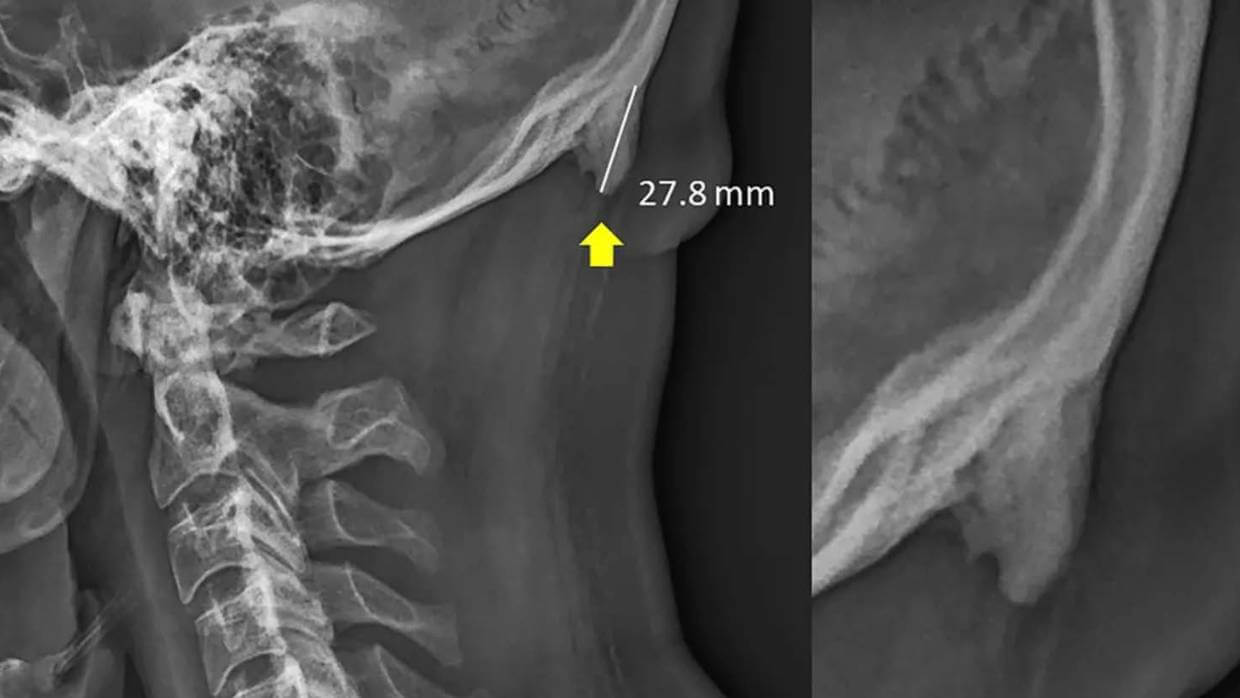

Так это выглядит на рентгене.

Один из самых удивительных фактов в этом исследовании является размер этих наростов, говорит Шахар. В среднем он считается довольно большим если речь идет о длине 3-5 миллиметров, однако в выборку ученых попали только случаи, когда речь шла о наростах размером минимум 10 миллиметров.